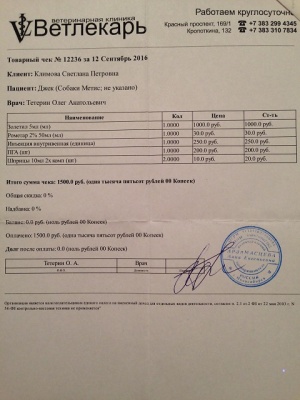

– кастрация по проекту «Все в моих руках», клиника Ветлекарь, хирург Тетерин Олег Анатольевич (чек 2, товарный чек 2, согласие на операцию – документ 2, рекомендации – документ 2-2) – 1500 руб.;

– кастрация по проекту «Все в моих руках», клиника Ветлекарь, хирург Тетерин Олег Анатольевич (чек 2, товарный чек 2, согласие на операцию – документ 2, рекомендации – документ 2-2) – 1500 руб.;

12.09.2016, перед началом пиара, проведена кастрация в клинике Ветлекарь, по льготной программе Все в моих руках. Кастрировал Джека сам Олег Анатольевич Тетерин.

12.09.2016, перед началом пиара, проведена кастрация в клинике Ветлекарь, по льготной программе Все в моих руках. Кастрировал Джека сам Олег Анатольевич Тетерин.